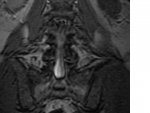

I got the CD and I think there is an angry guy inside me

But here is the on that is giving me the trouble. Think they will want to do a microdiscectomy

I got the CD and I think there is an angry guy inside me

But here is the on that is giving me the trouble. Think they will want to do a microdiscectomy